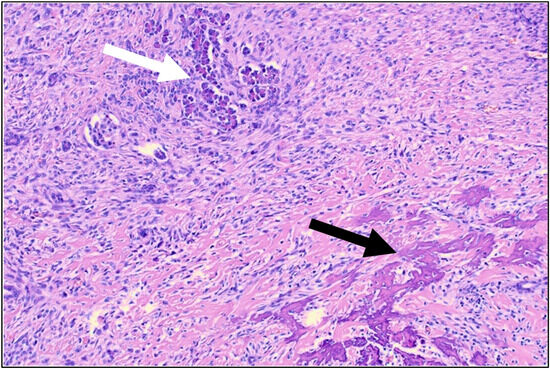

Rare Case of Squamous Cell Carcinoma Arising from an Intraosseous Epidermal Cyst: A Diagnostic Challenge

We report a rare case of squamous cell carcinoma (SCC) arising from an intraosseous epidermal cyst (EC) in the distal phalanx of the left thumb. A 76-year-old male presented with progressive thumb pain experienced over the previous six months. Radiography revealed a radiolucent [...] Read more.

We report a rare case of squamous cell carcinoma (SCC) arising from an intraosseous epidermal cyst (EC) in the distal phalanx of the left thumb. A 76-year-old male presented with progressive thumb pain experienced over the previous six months. Radiography revealed a radiolucent lesion without marginal sclerosis, and magnetic resonance imaging showed peripheral contrast enhancement with no solid components. Surgery revealed a bone-originating mass without adhesion to the surrounding skin or nail bed, which histopathological findings determined contained both cystic epithelium with laminated keratin and invasive keratinizing tumor cells, confirming SCC arising from an intraosseous EC. No primary lesion or lymph node enlargement was identified by postoperative computed tomography. Although wide resection and chemotherapy were proposed, the patient declined further intervention beyond the curettage performed during surgery, opting for close observation only. No recurrence or metastasis has been observed in the five years since the surgery. Intraosseous ECs are extremely rare, with malignant transformation even more uncommon. Accurate diagnosis requires histopathological confirmation, as imaging alone is insufficient. This case highlights the importance of considering intraosseous EC in the differential diagnosis of bone lesions and underscores the need for further case accumulation to clarify optimal management strategies. Full article